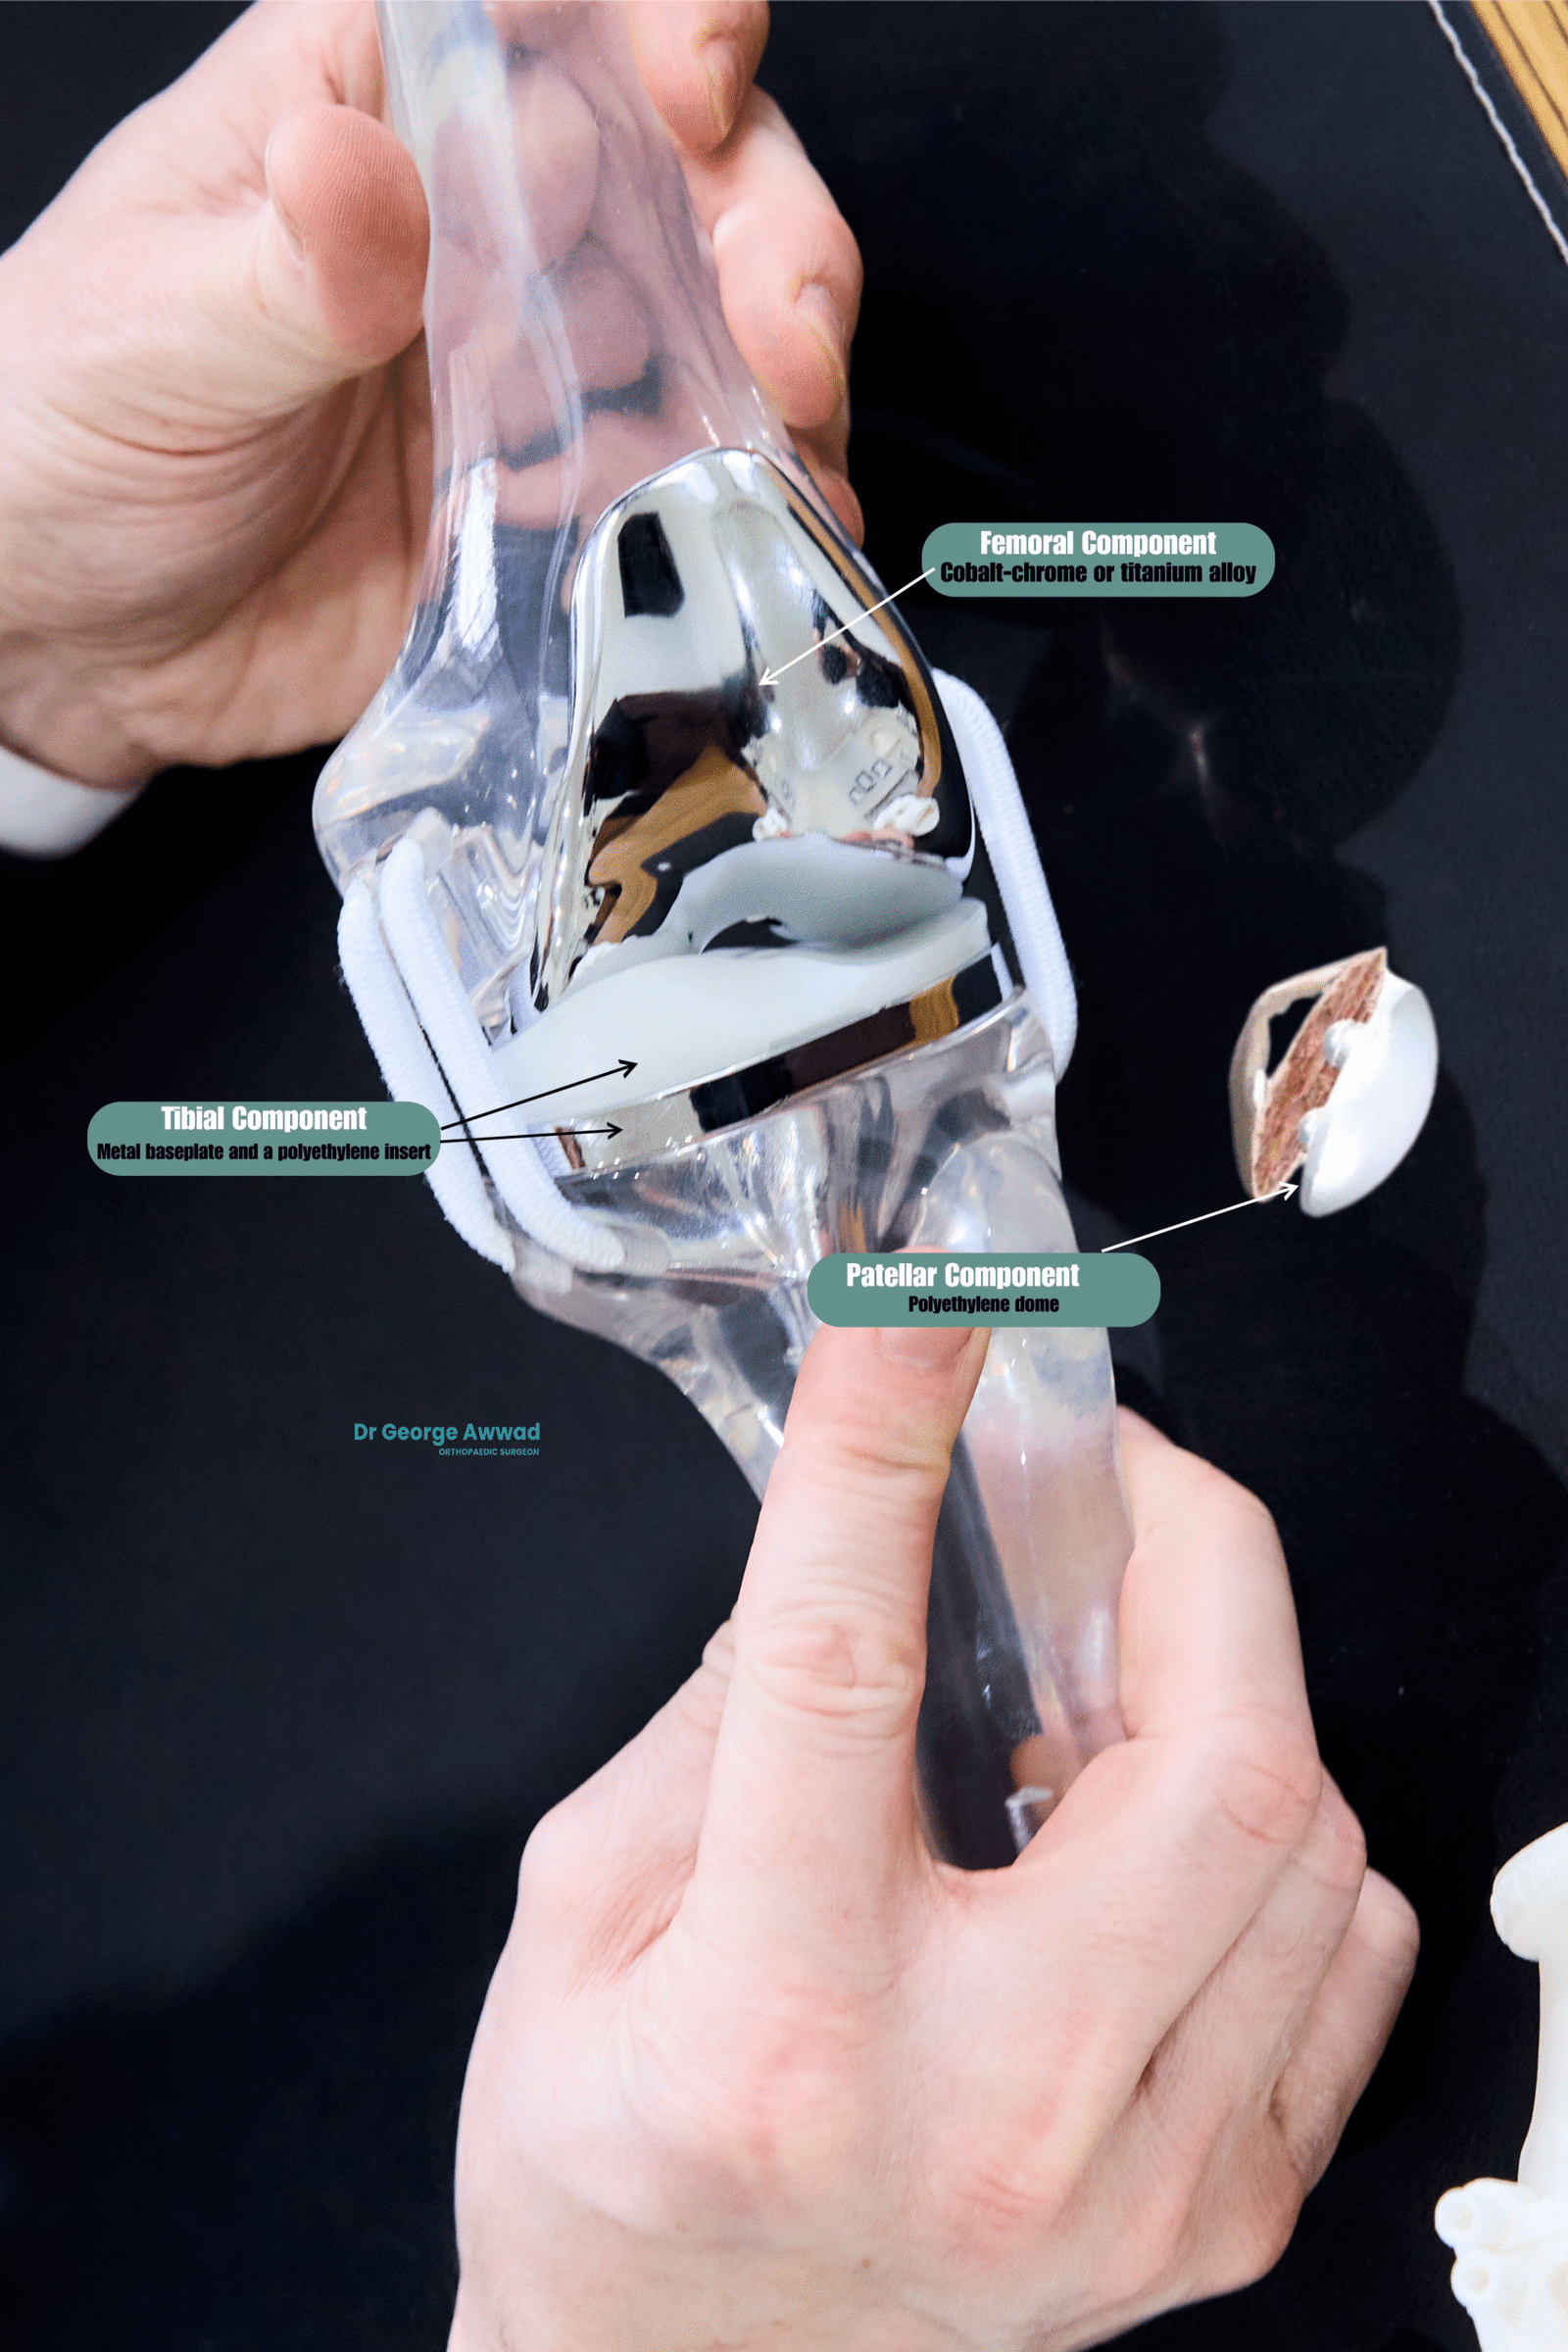

What types of knee implants are used in total knee arthroplasty?

Main components of a knee replacement implant

- Femoral component – This metal piece caps the end of the thigh bone (femur) and may be curved to match the natural shape of the femur. It allows smooth movement against the tibial component.

- Tibial component – Placed on top of the shin bone (tibia), this component consists of a metal baseplate and a polyethylene (medical-grade plastic) insert that acts as a cushion and bearing surface.

- Patellar component – In some cases, the underside of the kneecap (patella) is also resurfaced with a polyethylene dome to improve joint tracking and movement.

Implant materials and design

Knee replacement implants are made from biocompatible materials that are designed to last many years. Common materials include:

- Cobalt-chrome or titanium alloy for strength and durability in the femoral and tibial components

- Highly cross-linked polyethylene for the insert, offering improved wear resistance

- Cemented or uncemented fixation options, depending on patient bone quality and other factors

Some implant designs may include:

- Posterior-stabilised designs for patients with weak or absent cruciate ligaments

- Cruciate-retaining designs that preserve the posterior cruciate ligament for more natural knee movement

- Medial-pivot or rotating platform designs to allow more natural joint kinematics in selected patients

Customised implant selection

Dr Awwad takes a personalised approach to selecting your knee implant. A pre-operative imaging and planning process allows him to create a surgical plan tailored to your unique anatomy, ensuring that the chosen implant offers optimal alignment, fit, and function. Robotic assistance and kinematic alignment techniques may also support more accurate placement and balance of the implant.

Each patient’s implant choice is made with the goal of restoring joint stability, range of motion, and long-term durability, supporting you to return to daily activities with confidence.